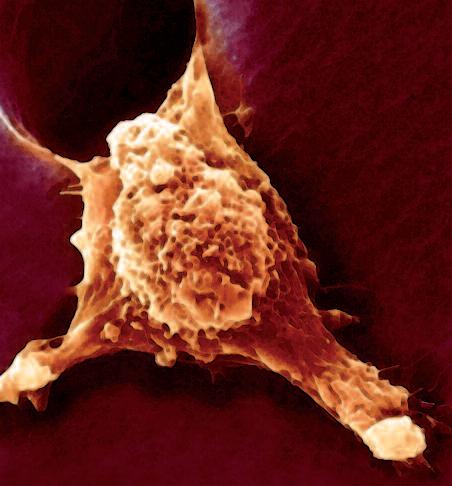

La pagina a fianco mostra l'immagine di una cellula tumorale reale, visualizzata al microscopio elettronico, che ingrandisce questa cellula 6500 volte rispetto alle sue normali dimensioni. Questo tipo di cellula prende il nome di carcinoma, cioè derivante da cellule epiteliali, il tipo di cellule che rivestono sia le superfici interne (polmoni, intestini) che esterne (pelle) del corpo.

Grazie a questo ingrandimento si possono identificare chiaramente alcune delle caratteristiche di tutte le cellule tumorali: a) l'enorme nucleo cellulare dalla forma insolita che spiega la loro grande capacità di riprodursi e b) la struttura non uniforme, complessa della superficie cellulare, che riflette una forte attività di secrezione di sostanze prodotte dalle cellule tumorali.

Una delle più importanti molecole secrete dalle cellule tumorali in grandi quantità sono gli enzimi a ‘forbice’ che digeriscono il collagene. Sono aggiunti graficamente a questa immagine, sotto forma di strutture simili ad un ‘pacman’ rosso.

La foto nella pagina a fianco mostra una cellula cancerogena ad un microscopio.

Il corpo di questa cellula tumorale in migrazione si espande nella direzione del suo movimento all’interno del tessuto. Può formare una struttura ‘tentacolare’ che trascina la cellula tumorale lungo la superficie, in questo caso, di un vaso sanguigno.

Gli enzimi che digeriscono il collagene sono aggiunti per illustrare il processo mediante il quale qualsiasi ostacolo sul cammino di questa cellula tumorale viene superato.